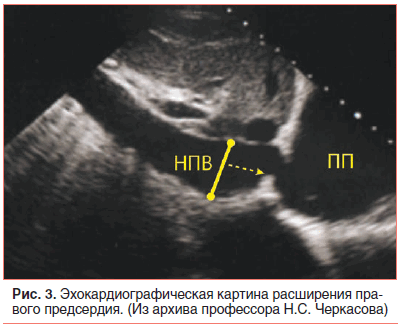

В возрасте 2,5 мес. жизни подтвержден диагноз: Врожденный порок сердца (ВПС): ОАП. На ЭХО-КГ: ОАП 3,5 мм со сбросом крови в легочную артерию с градиентом 4 мм рт. ст., аневризма межпредсердной перегородки (АМПП) и открытое овальное окно 3,5 мм со сбросом крови справа налево, высокая ЛАГ 89 мм рт. ст. с расширением правого предсердия (ПП) (рис. 3).

За время наблюдения в течение 1 года систолическое давление в легочной артерии (СДЛА) имело положительную динамику. На ЭКГ регистрировался синусовый ритм, миграция водителя ритма, электрическая ось сердца резко отклонена вправо, â=+150°, ЧСС 120–150 в минуту, PQ 0,1. На ЭХО-КГ отмечается: состояние после лигирования ОАП, проток закрыт герметично, пограничные размеры правых камер сердца (правый желудочек 1,77 см; ПП 1,76 см). Глобальная сократимость левого желудочка не нарушена. Фракция выброса SF 60%. Эктопическая хорда в полости левого желудочка. Митральная регургитация 0–I степени. Трикуспидальная регургитация I степени. Легочная артерия 1,46 см, СДЛА 46 мм рт. ст. Перикард без особенностей. Максимальный градиент давления на Ао 8,1 мм рт. ст. Сатурация О2 94%.